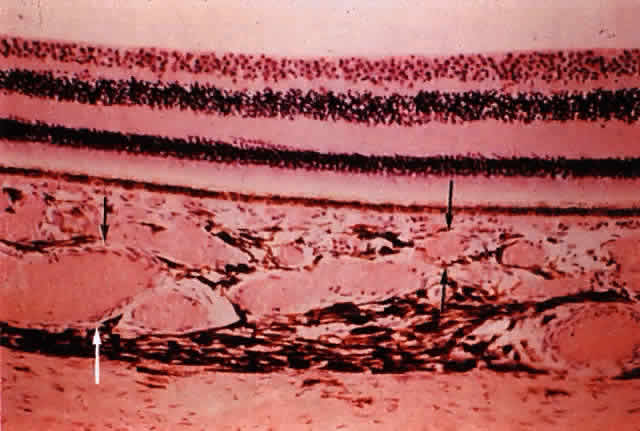

The funduscopic appearance of ischemic lesions in the choroid has been recognized since the early 19th century. In 1904, Elschnig67 described areas of circumscribed secondary RPE loss (Elschnig's spots), which are now recognized to be signs of ischemic infarcts arising from acute occlusion of the choriocapillaris or precapillary choroidal arterioles (Figs. 32, 33, and 34). Multifocal acute ischemic choroidopathy results from acute ischemic lesions of small choroidal arterioles, whereas geographic choroidopathy is due to an occlusion of larger choroidal arterioles or small arteries.47Triangular or wedge-shaped choroidal lesions appear to be three-sided, the apex pointing posteriorly and the base anteriorly. They are believed to represent evidence of occlusion of larger choroidal vessels. Occlusion of the long or short posterior ciliary arteries or their branches results in triangular defects. Triangular defects caused by obstruction of the short posterior ciliary arteries are more numerous, more irregular, and usually smaller. If the triangles become confluent, they may produce hemiatrophy of a quadrant.47,68

Fig. 33. Photomicrograph of area corresponding to that in Figure 31 shows ischemic atrophy of outer retina and retinal pigment epithelium. (H & E, × 25)

Fig. 34. Flat preparation showing focal atrophy of choriocapillaris in eye with cobblestone degeneration. (AFIP Neg 75-5513; PAS, × 42)